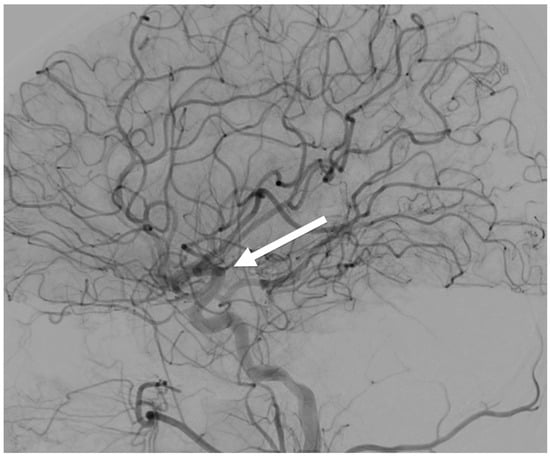

| 2D radiography (see Figure 5, Figure 6, Figure 11 and Figure 16) | See detector a, b, c resolution | 1 s to 2 min/1–360 | ~50/50/50 | SID 50–1100/ everything else is variable |

| 3D dynamic imaging stereovideography (Figure 5, Figure 6 and Figure 9) | 20–200 μm Static or moving image intensifiers with high-speed cameras | 1 s, as required by IR/10–10000 | 0.02–1.1 mSv min−1/0.08–0.9 mSv min−1/0.02–0.08 mSv min−1 | 50–1100 /10–500/variable VD and VH/0.02–0.2 |